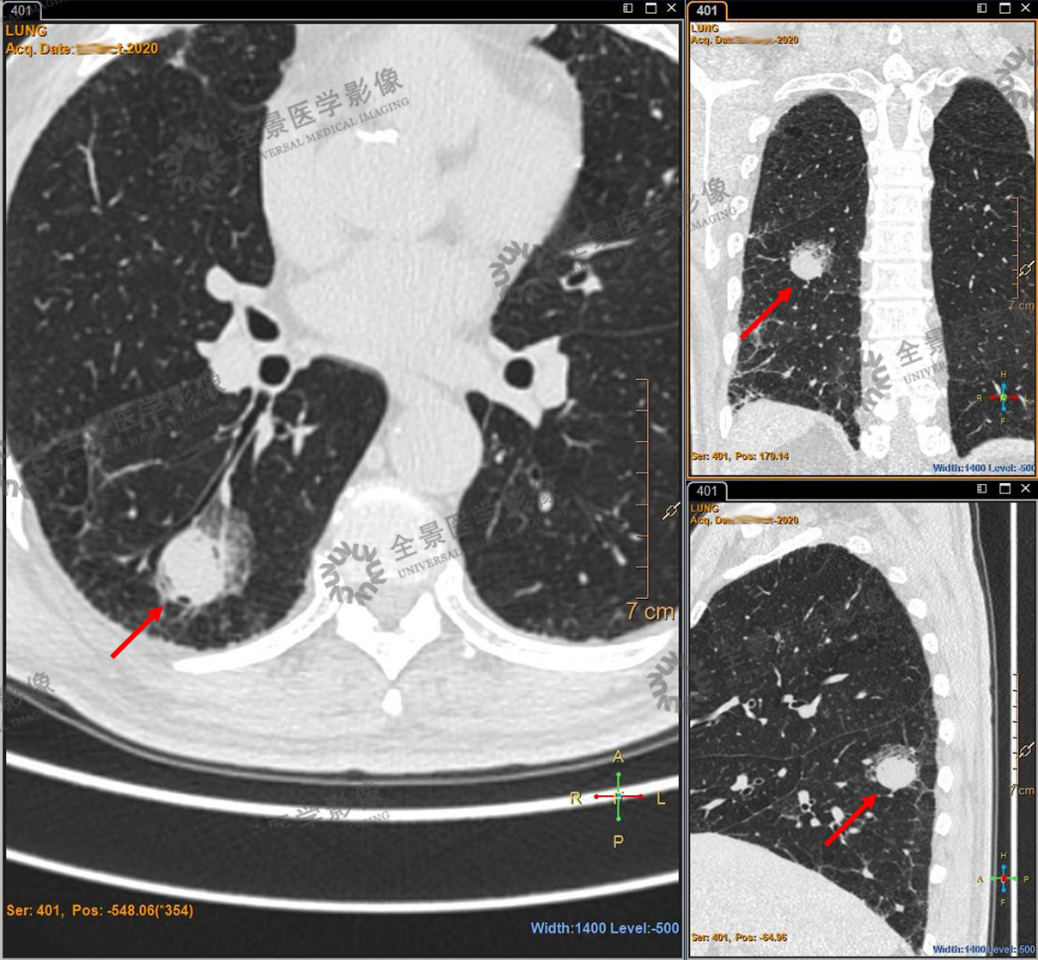

主写报告的富鹏主治医师和负责审核的李德鹏主任仔细研读了蒋老先生的片子,结合CT平扫和PET成像,最终认为从病灶形态、与周围组织的关系以及病灶代谢特点都不足以支持恶性肿瘤的诊断,更有可能是良性病变。

PET/CT 右肺下叶背段实性结节,FDG呈轻度摄取